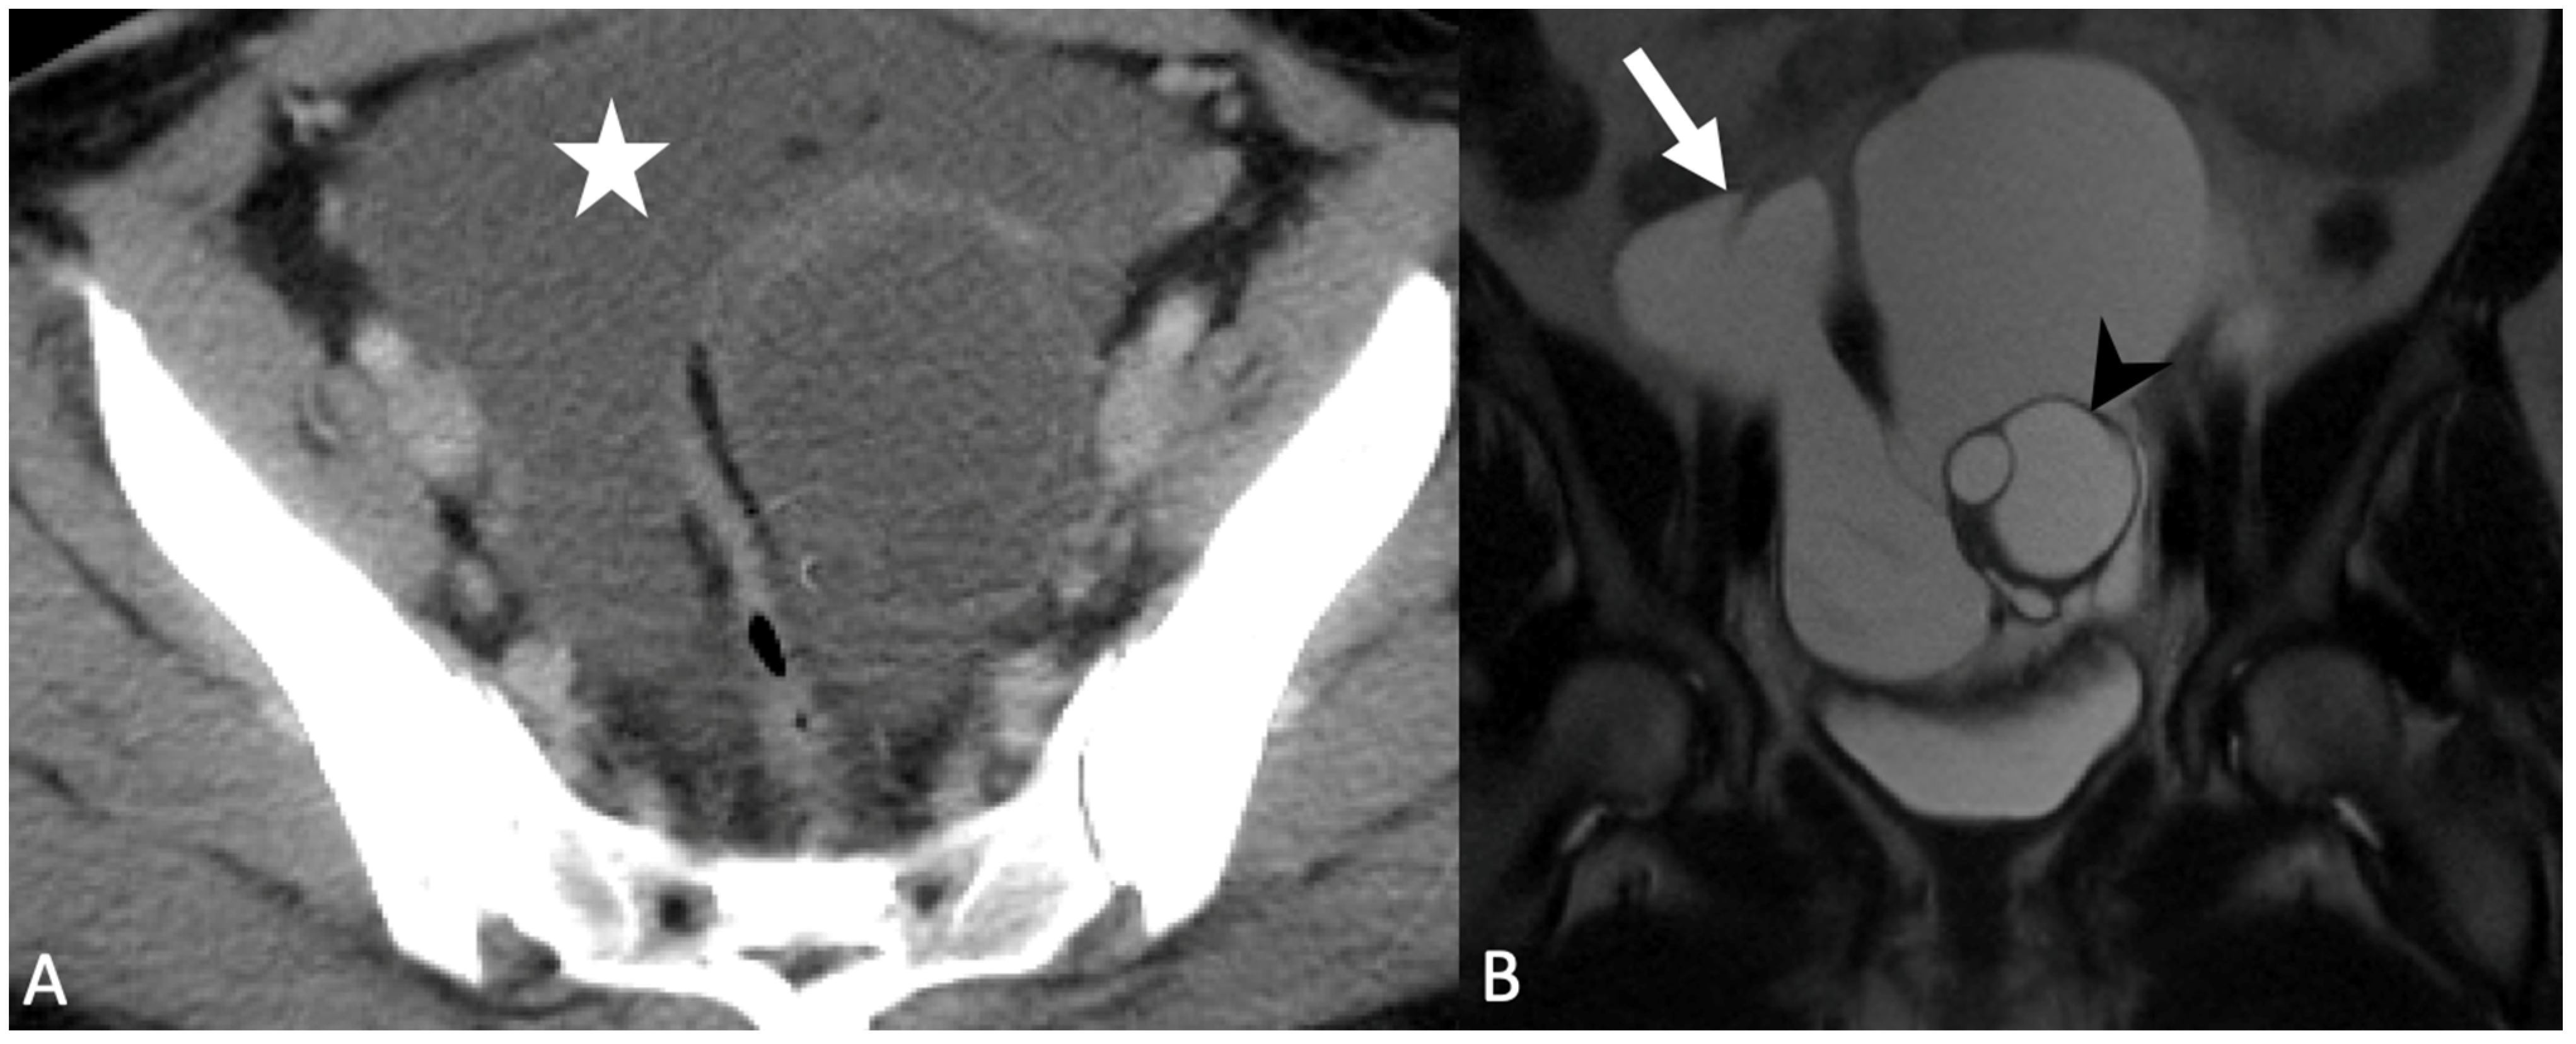

5.2. Uterine Lesions

5.2.2. Leiomyoma